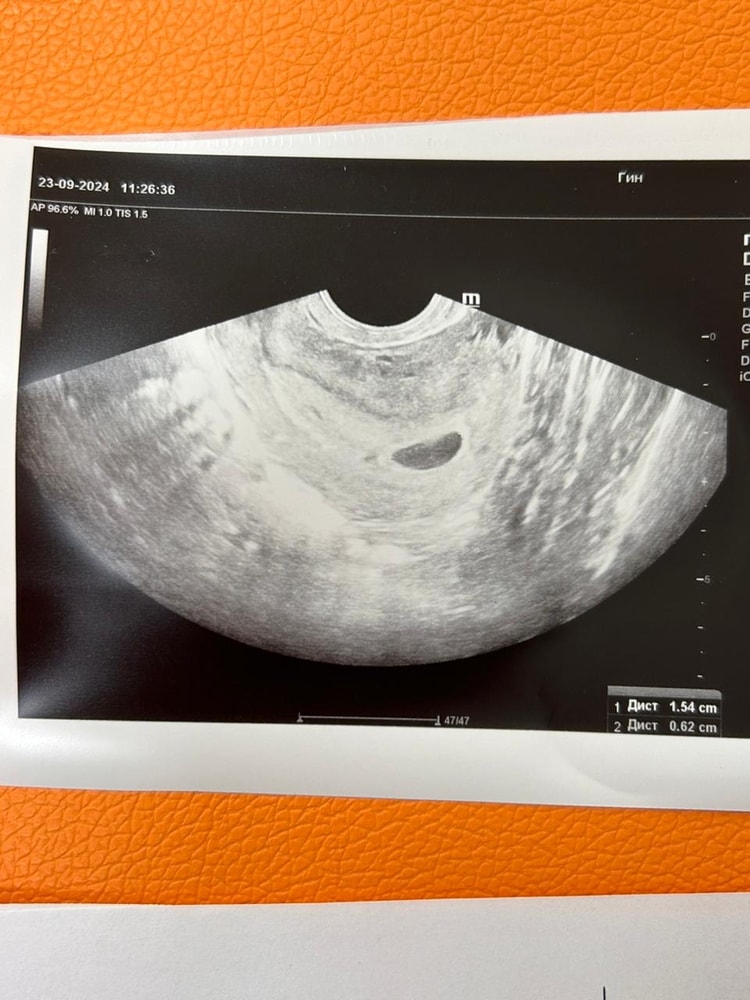

Вот 1 узи, где аппарат не очень..

мне Вот при таком узи врач утверждал что там НИЧЕГО нет)))